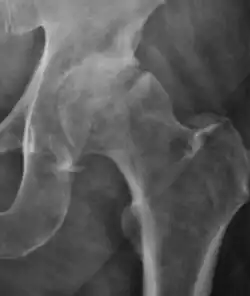

Plain radiography allows us to categorize the hip as normal or dysplastic or with impingement signs (pincer, cam, or a combination of both). Besides these, pathologic processes like osteoarthritis, inflammatory diseases, infection, or tumors can also be identified (Figure 1).[1]

Figure 1.

Osteoarthritis

In adults, one of the main indications for radiographs is the detection of osteoarthritic changes (Figure 1(e)). Nevertheless, radiographs usually detect advanced osteoarthritis that can be graded according to the Tönnis classifications. The grading system ranges from 0 to 3, where 0 shows no sign of osteoarthritis. Intermediate grade 1 shows mild sclerosis of the head and acetabulum, slight joint space narrowing, and marginal osteophyte lipping. Grade 2 presents with small cysts in the femoral head or acetabulum, moderate joint space narrowing, and moderate loss of sphericity of the femoral head. Grade 3 is the severest form of osteoarthritis, which manifests as severe narrowing of the joint space, large subchondral cyst with productive bone changes that may lead to deformity of the bone components of the joint, while secondary osteoarthritis due to calcium pyrophosphate deposition can be diagnosed when calcification of hyaline cartilage and fibrocartilage is detected.[1]